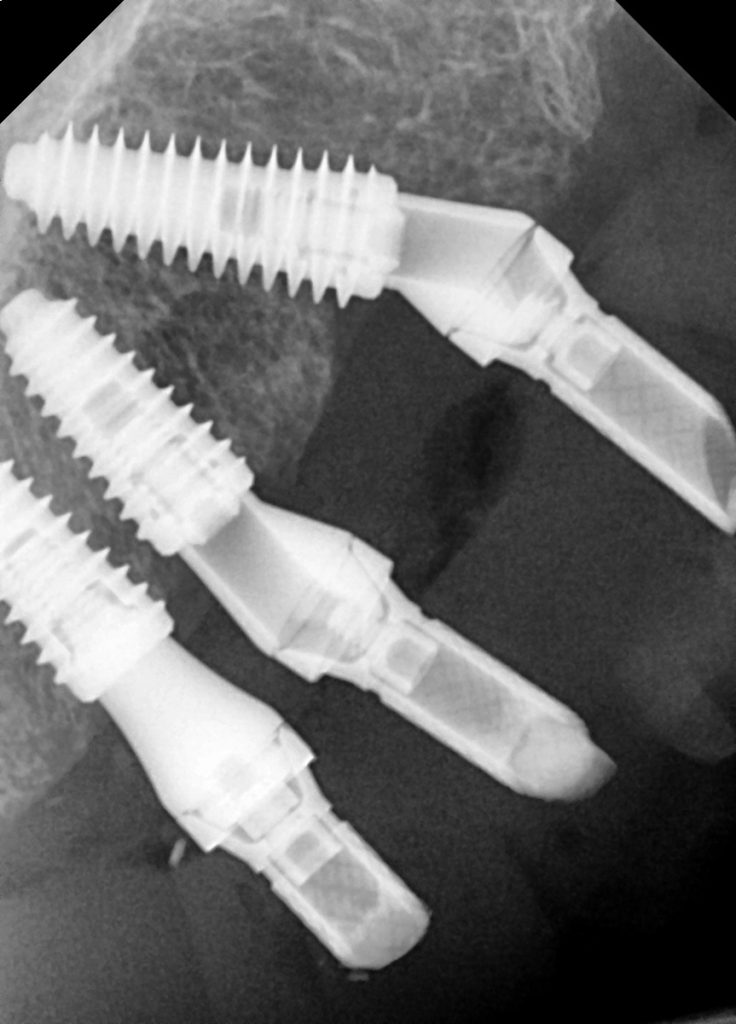

The patient really didn’t want a lower temporary denture, so we removed his lower teeth, placed implants on the same day and also immediately loaded on the same day too, thanks to our lab technician.

SK: We removed all lower teeth and placed four implants, which we immediately loaded using the skills of our lab technician.

We left the upper arch for three months, then placed our implants and immediately loaded. We were able to do this in a clean and settled site.

The occlusion was carefully managed to ensure loading was spread out along the whole bridge rather than it being heavy in certain areas. This allowed a more even distribution of loading across all implants.

We also explained the concept of a shortened dental arch as we couldn’t place the implants too distal in the 6/7 areas due to insufficient bone. The patient was fully aware that the full arch bridge was going to be 6-6 in the final prosthesis and 5-5 in the temporary prosthesis in order to reduce any cantilever force and reduce fractures.